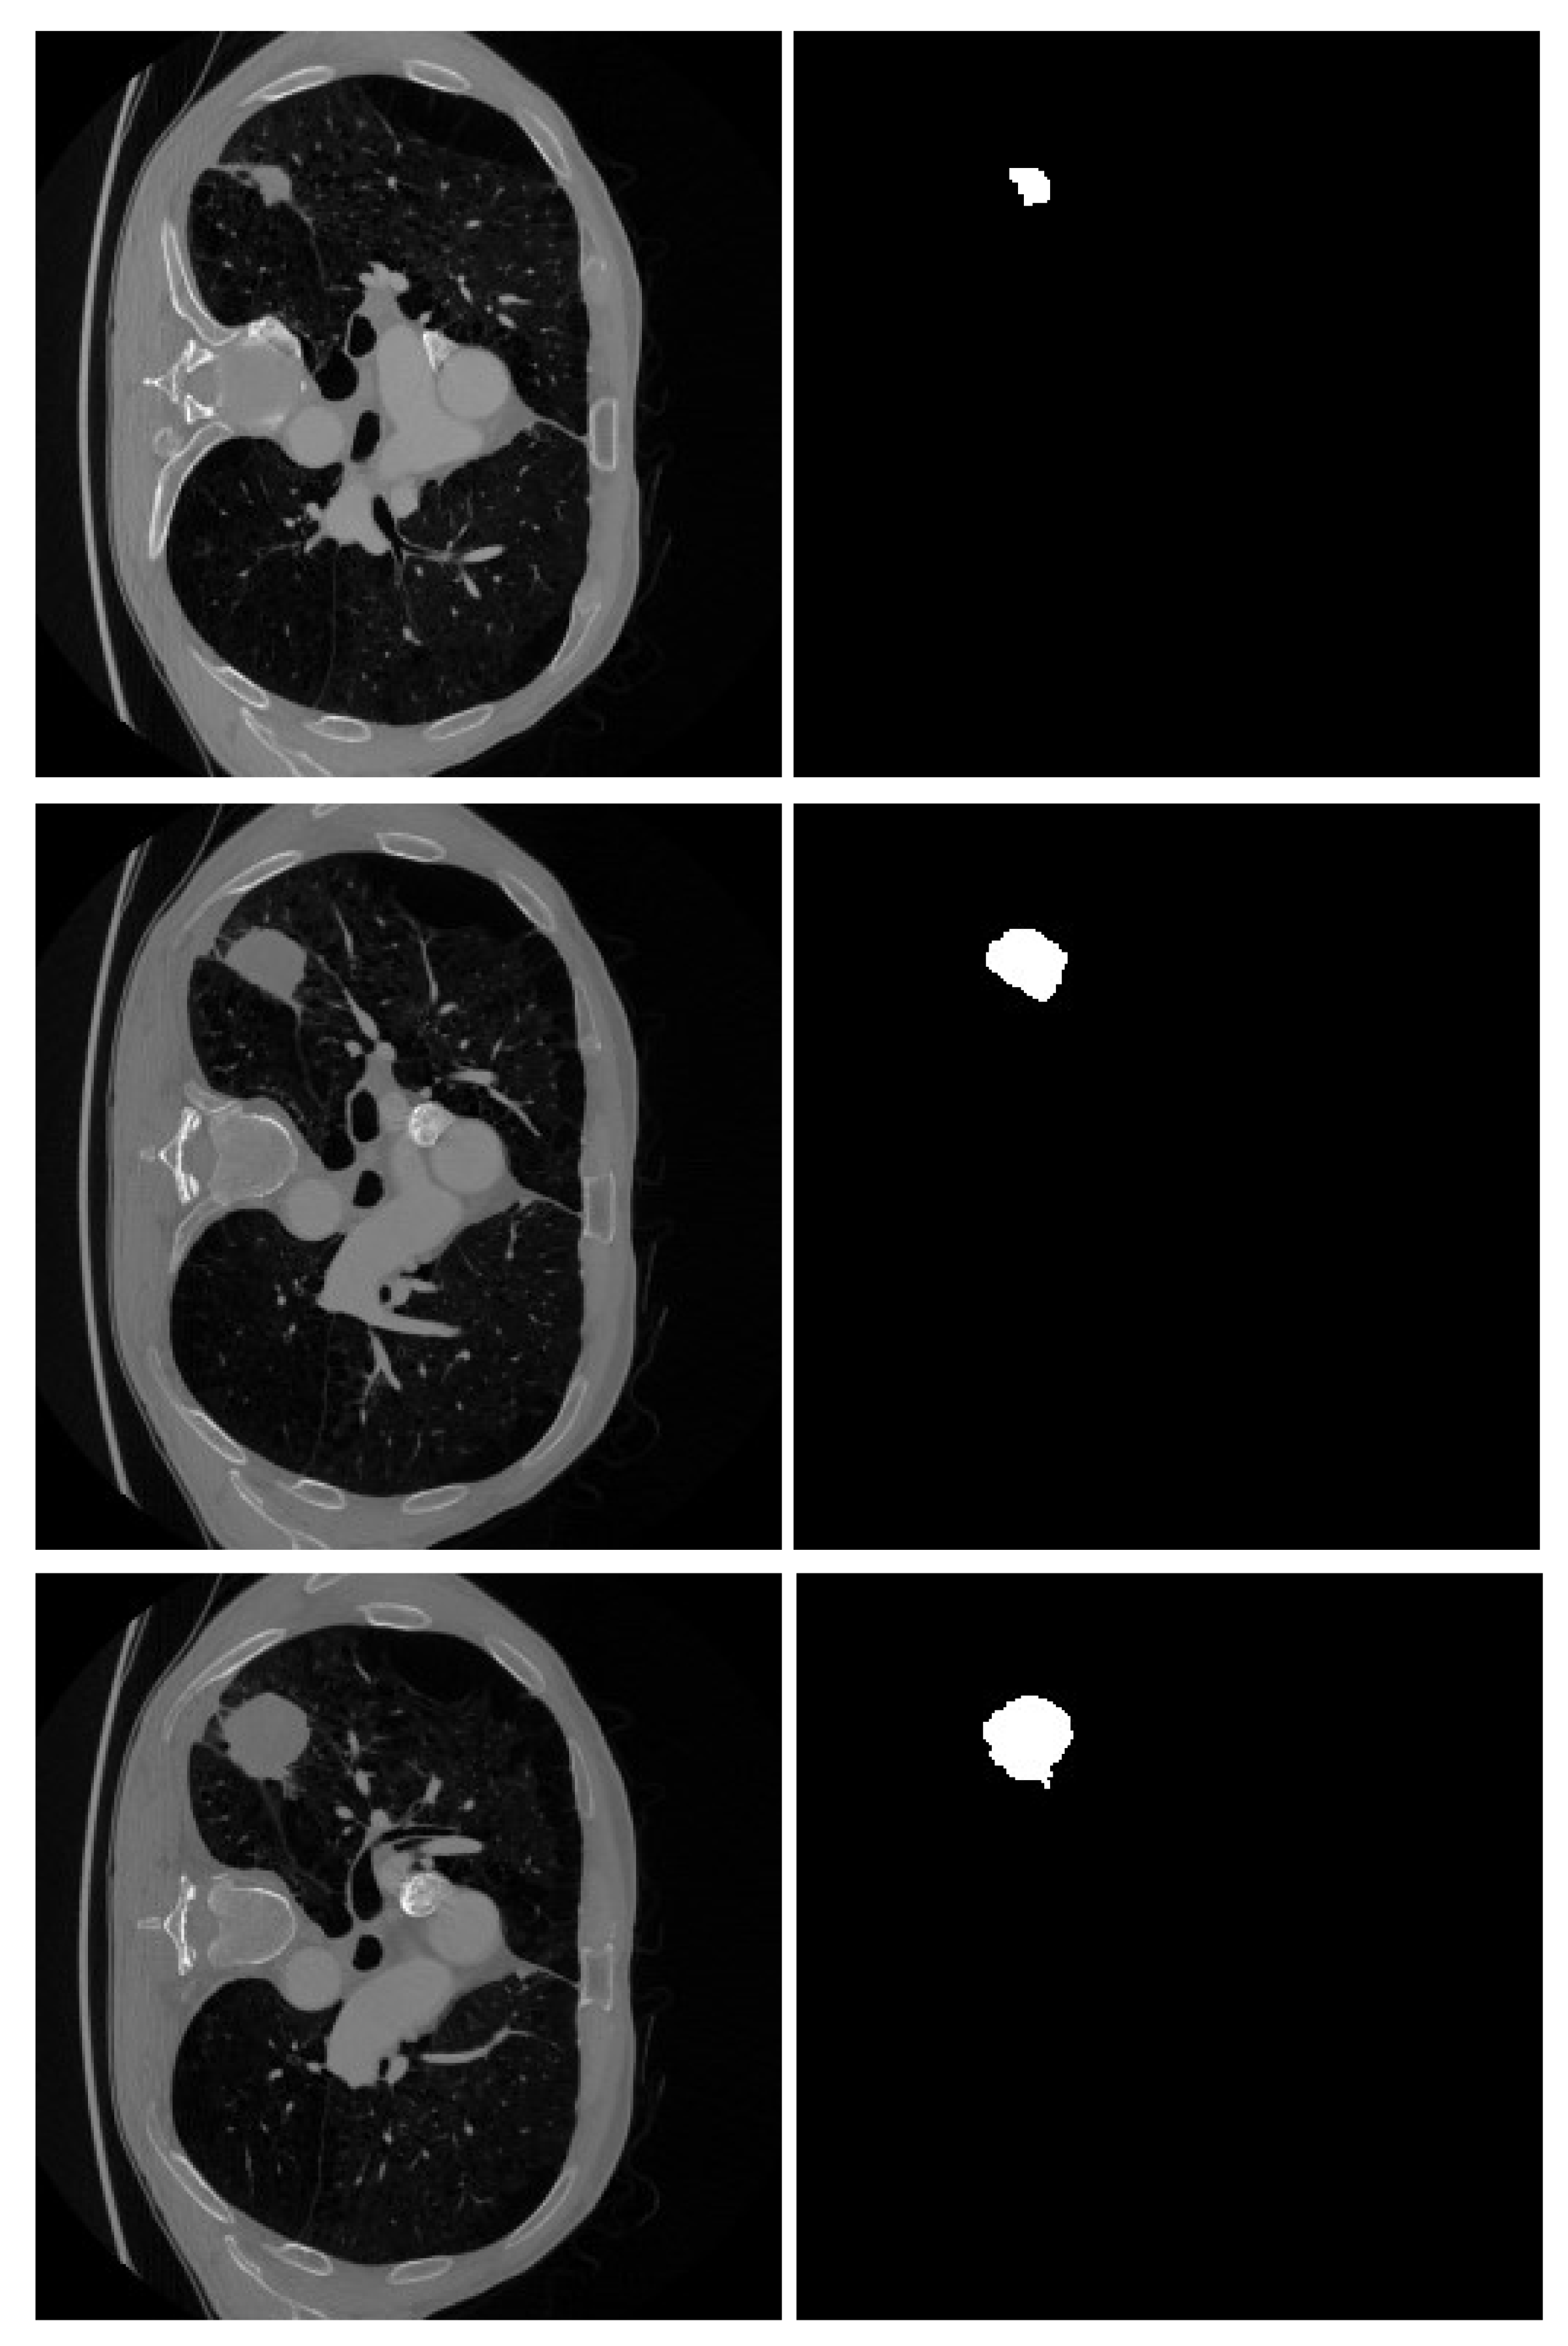

The experimental studies were conducted using data from a public Kaggle dataset [33]. A total of 3296 images were selected from this dataset, which contains over 14,000 images along with their corresponding masks. The initial step involved dividing the dataset into two categories: patient/healthy (positive/negative). Each image is paired with a corresponding mask image. These mask images are black-and-white and highlight the tumor region, if present, on the original image, as illustrated in the Figure 2.

Figure 2. Some samples of lung CT images and their region of tumor as a black-white mask.